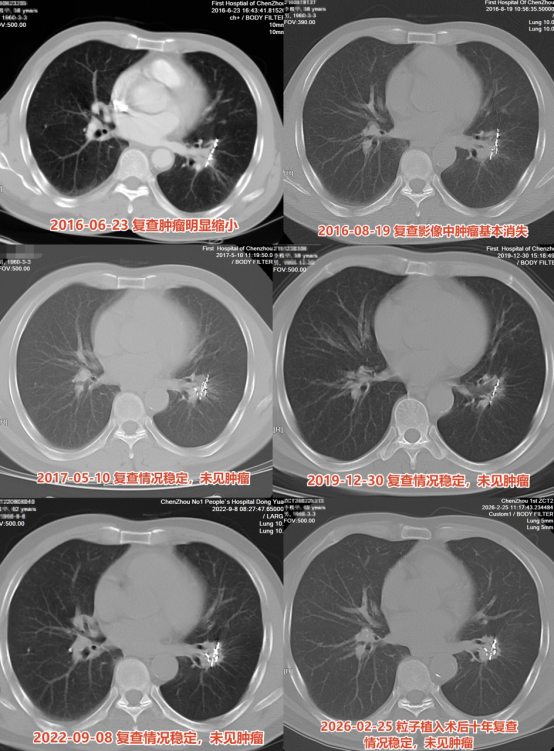

65岁爷爷患肺癌晚期存活10年 精准治疗创奇迹。今年春天,65岁的李伯伯来到郴州市第一人民医院影像专家门诊进行肺癌治疗后的随访复查。十年前,他因咳嗽到医院就诊,CT报告显示左肺下叶恶性肿瘤并对侧肺叶内转移;随后住院完善检查及病理,最终诊断为左肺下叶肺鳞癌 T2N0M1 IV期。

但李伯伯的治疗团队没有拘泥于晚期肺癌的姑息治疗,而是根据他的经济条件和治疗意愿,召集多学科团队反复讨论后,制定了一套组合方案:CT引导下放射性粒子植入术,联合GP方案(吉西他滨+铂类)化疗。